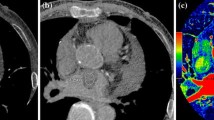

For comparison of CM and thrombus with the naked eye, significant differences were observed in the adjacent structures. The thrombus group had more hydrothorax (30.0% vs. 8.5%, p = 0.004), pericardial effusion (42.0% vs. 18.6%, p = 0.008), and heart enlargement (82.0% vs. 55.9%, p = 0.004). For lesions, lesion surface and location were significantly different between the two groups (p = 0.004, p = 0.000, respectively). The CM group had more coarse surfaces (59.3%) while the thrombus group had more smooth surfaces (68%). More thrombi (48%) were located in the Left atrial appendage (LAA), while most CMs (88.1%) are in left atrial (LA). Calcification (p = 0.672), homogeneous density (p = 0.371), and enhanced CT value (0.370) showed no significant difference in the two cohorts (Fig. 3]. More information is shown in Table 2.